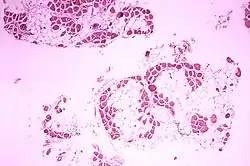

- biopsja mięśnia (cechy miopatii, brak lub nieprawidłowa dystrofina w badaniu immunocytochemicznym)